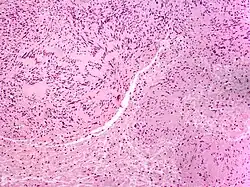

| Solitary circumscribed neuroma | |

A neuroma (/njʊəˈroʊmə/; plural: neuromata or neuromas) is a growth or tumor of nerve tissue.[1] Neuromas tend to be benign (i.e. not cancerous); many nerve tumors, including those that are commonly malignant, are nowadays referred to by other terms.